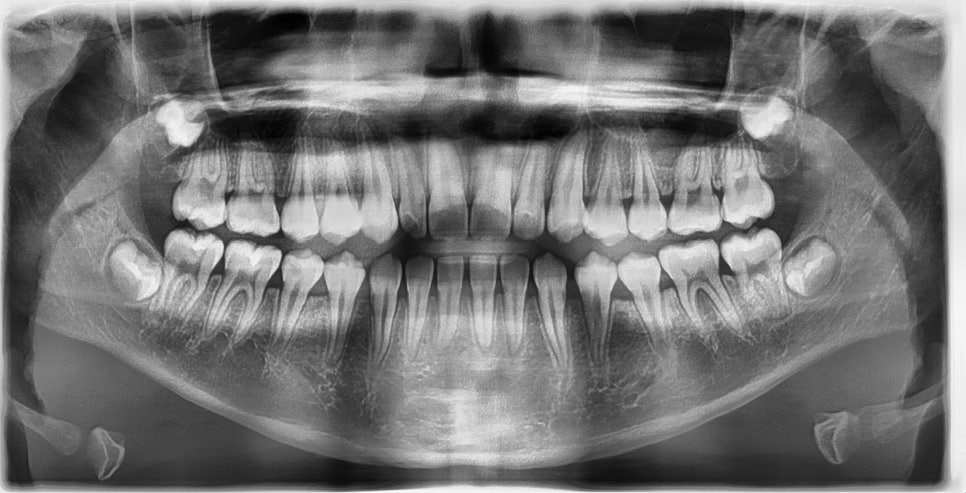

2024.8.12. 초진

초진시 위아래 앞니끼리 맞물리는 절단교합 양상을 보이고 있었으며 아래 앞니는 치아 사이가 많이 벌어져 있었습니다. Cephalometric x-ray 상 아래턱이 발달한 제 3급 부정교합 (주걱턱) 양상을 보이고 있었고, 수완부사진 성장판 검사 결과 SMI 7~8단계에 해당하여 사춘기 최대 성장기는 지난 상태였습니다.

Cephalometric X-ray